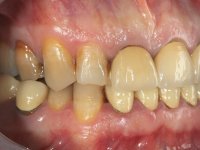

Paciente do sexo masculino, com 42 anos de idade, não fumador. Apresentava uma reabilitação metalo -cerâmica feita há mais de 10 anos com exposições radiculares e infiltrações. No maxilar superior apresentava uma coroa no 1.1,uma ponte de dois elementos no 2.1 e 2.2.e uma ponte de 4 elementos nos dentes 2.4,2.5,2.6 e 2.7 com o 2.6 como pôntico. Os dentes 1.6/1.5/1.4/1.3/1.2/1.1/2.1/2.2/2.3/2.4/2.5 e 2.7 apresentam tratamento endodôntico radical com o 2.4/2.5 e 2.7 a necessitarem de ser refeitos. No maxilar inferior apresentava uma ponte metalo-cerâmica de 4 elementos nos 4 incisivos e uma ponte de 3 elementos (3.3 e 3.4) com um dente supranumerário como pôntico. Os dentes 4.6/4.5 e 4.2 apresentavam tratamento endodôntico com o 4.2 a necessitar de ser refeito. Os dentes 4.3 e 4.4 apresentavam extensas cáries linguais com algum comprometimento mesial. As peças protéticas apresentavam-se infiltradas com exposição radicular associada. Apresentava uma D.V.O. diminuída e uma mordida cruzada lado direito. O paciente tinha uma satisfatória saúde periodontal e uma boa higiene oral.

A primeira acção terapêutica foi tentar melhorar o tratamento endodôntico dos dentes (2.4/2.5/4.2)). A sua manutenção em boca seria condicionada pelo sucesso desta intervenção. Seguidamente foram feitas impressões em alginato e registo inter-maxilar em silicone para confeção em laboratório de uma ponte provisória em acrílico com reforço. O objetivo desta ponte provisória seria ensaiar o aumento da D.V.O. e descruzar a mordida do lado direito. Foi utilizado um monobloco de 13 dentes com o dente 2.6 com o pôntico. As coroas e as pontes foram removidas e os remanescentes coronários foram repreparados. A ponte provisória foi rebasada primeiramente com acrílico auto-polimerizável e de seguida com resina composta. Após 2 semanas de permanência em boca, foram feitas as impressões para confeção da ponte provisória inferior também realizada em laboratório. Especial cuidado foi colocado na remoção das coroas antigas, sendo feito primeiramente um corte axial que permitiu que fossem removidas de uma forma menos traumática. A temporização foi feita durante 8 semanas, permitindo que os tecidos gengivais estabilizassem posicionalmente. As impressões definitivas foram realizadas após afastamento gengival utilizando a técnica do fio único impregnado. Foi utilizada a técnica de dupla mistura com dupla viscosidade (putty soft e light).Simultaneamente foi realizada a recolha das relações inter-maxilares e o registo com arco facial. Foram confecçionados os modelos de trabalho e feita a sua correta montagem em articulador semi-ajustável. Em seguida foram feitas infra estruturas em zircónia que posteriormente foram revestidas por cerâmica. A prova de “biscoito” foi realizada em boca para avaliação estética e funcional sendo também avaliado o seu assentamento e ajuste. A reabilitação definitiva foi cimentada em boca utilizando um cimento de ionómero de vidro reforçado por resina.